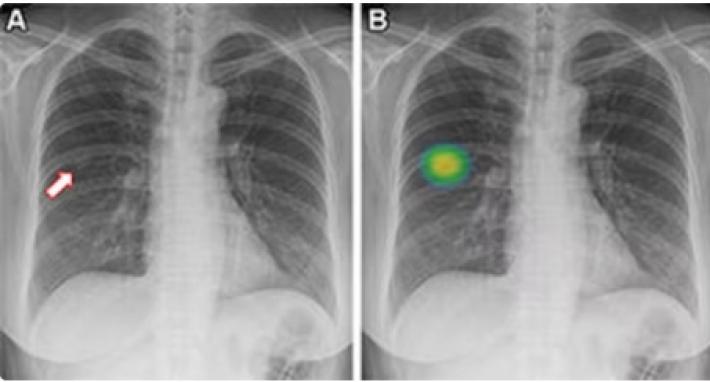

Utilizzando una semplice immagine radiografica del torace, l’intelligenza artificiale (AI) è in grado di identificare i non fumatori ad alto rischio di cancro ai polmoni, la causa più comune di morte per cancro, secondo uno studio condotto presso la Boston University School of Medicine, che verrà presentato la prossima settimana al meeting annuale della Radiological Society of North America (RSNA).

Circa il 10-20% dei casi di cancro ai polmoni si verifica in «non fumatori», persone che non hanno mai fumato o hanno fumato meno di 100 sigarette in tutta la loro vita. Inoltre, l'incidenza del cancro ai polmoni tra i non fumatori è in aumento, e senza una precoce rilevazione attraverso lo screening, quando vengono scoperti, questi tumori tendono ad essere più avanzati rispetto a quelli trovati nei fumatori, per i quali sono invece raccomandati gli screening periodici. I ricercatori hanno quindi sviluppato e testato uno strumento basato su intelligenza artificiale per verificare se potesse identificare i non fumatori ad alto rischio di cancro ai polmoni, basandosi sulle lastre toraciche nelle loro cartelle cliniche. «Un grande vantaggio del nostro approccio è che richiede solo un’immagine di una singola lastra toracica, uno dei test più comuni in medicina e ampiamente disponibile nelle cartelle cliniche», spiegano gli autori. Il modello «CXR-Lung-Risk» è stato inizialmente sviluppato utilizzando 147.497 lastre toraciche di 40.643 fumatori asintomatici e non fumatori. I ricercatori hanno poi convalidato il modello testandolo su un gruppo separato di non fumatori sulla base di lastre toraciche ambulatoriali nel 2013-2014. L’esito principale era l’incidenza del cancro ai polmoni a sei anni. Dei 17.407 pazienti (età media 63 anni) nello studio, il 28% è stato considerato ad alto rischio dallo strumento, e il 2,9% di questi pazienti ha successivamente ricevuto una diagnosi di cancro ai polmoni. Le persone che secondo lo strumento erano ad alto rischio di tumore presentavano un rischio più che doppio di sviluppare il cancro ai polmoni. «Questo strumento di intelligenza artificiale apre la porta allo screening opportunistico per i non fumatori ad alto rischio di cancro ai polmoni, utilizzando le lastre toraciche esistenti nel registro elettronico delle cartelle cliniche», conclude l’autore principale Michael Lu. «Poiché i tassi di fumo diminuiscono, approcci per rilevare precocemente il cancro ai polmoni tra coloro che non fumano diventeranno sempre più importanti».